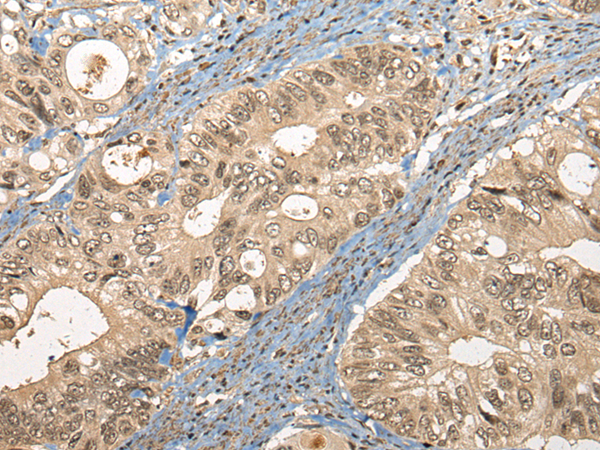

IHC positive control: |

Human liver cancer and human colorectal cancer |